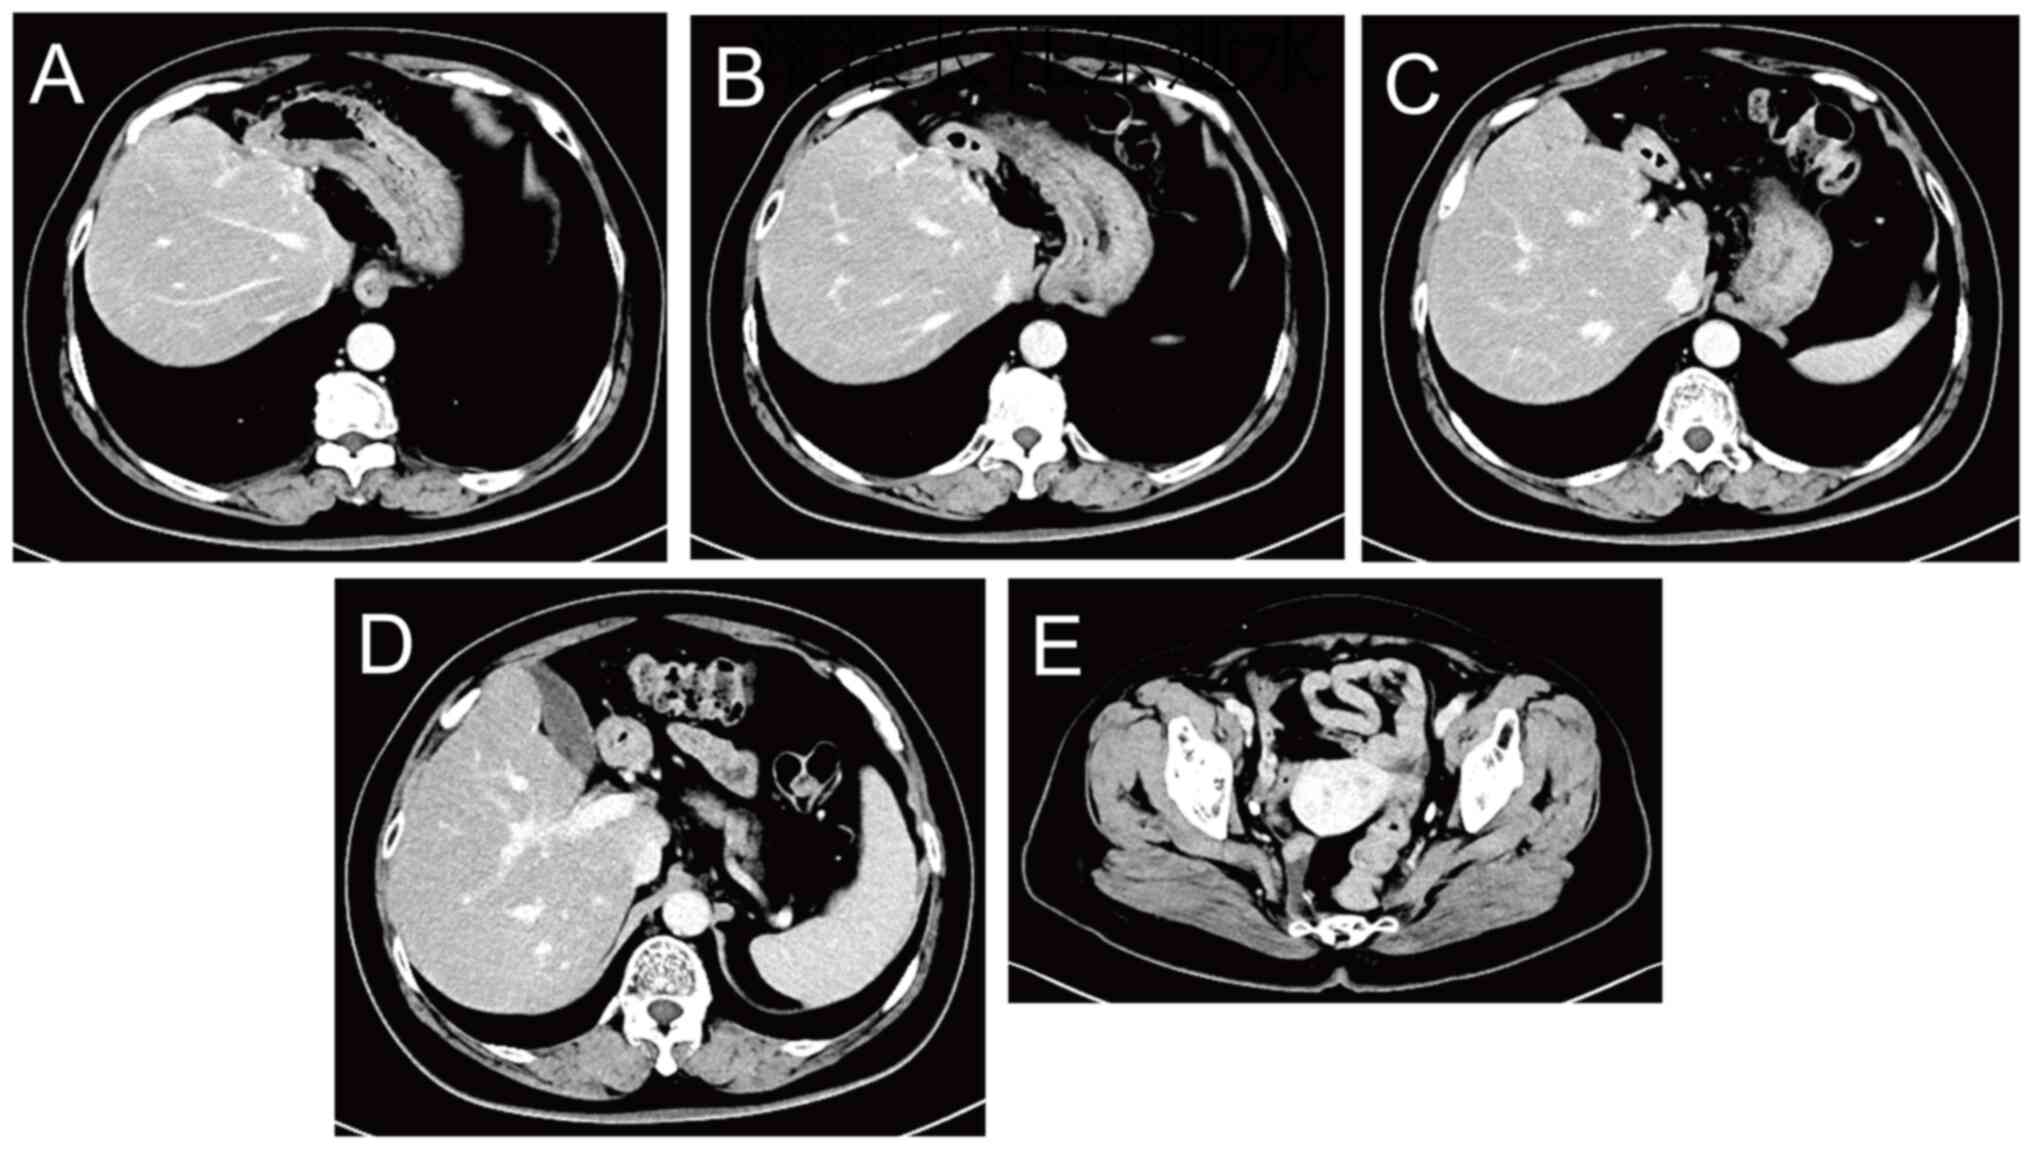

Images captured during colonoscopy

performed on October 17, 2023.

Figure 2.

Images captured during colonoscopy performed on October 17, 2023.